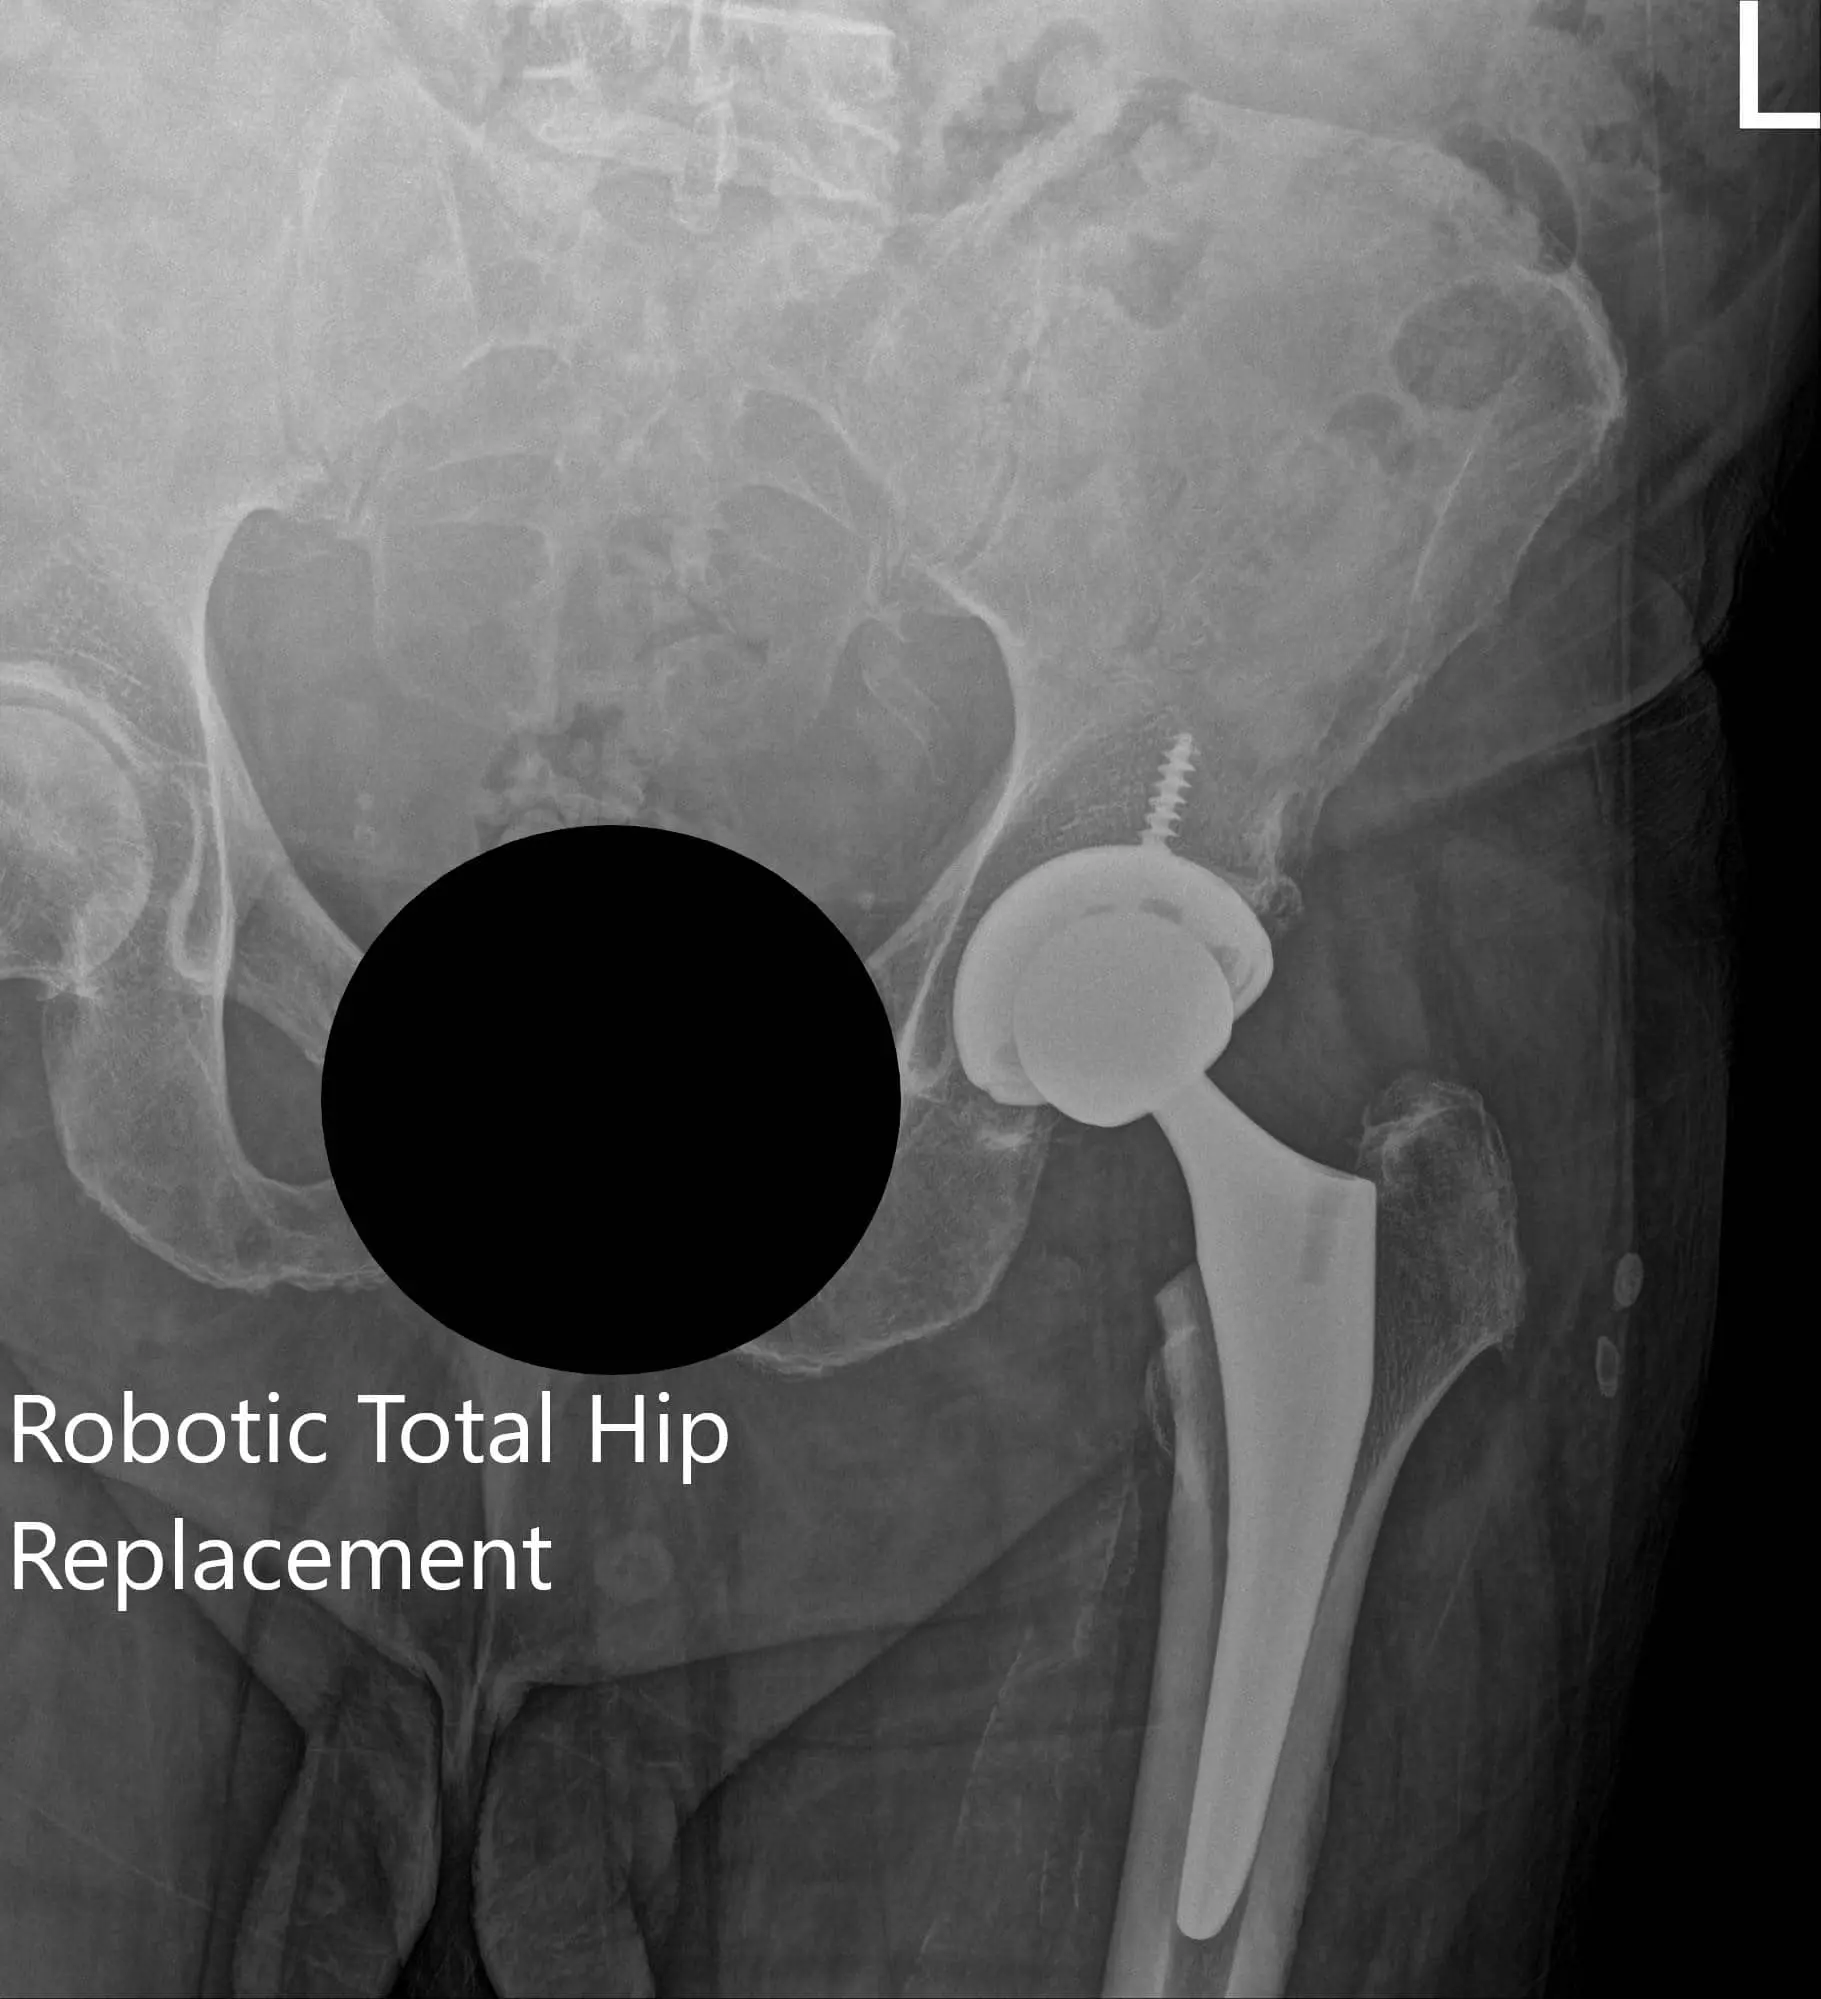

Postoperative X-ray of the left hip showing AP and frog-legged lateral view

Postoperative X-ray of the left hip showing AP and frog-legged lateral view - img 2